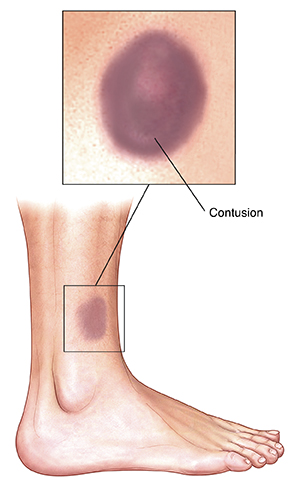

What is a contusion?

A contusion is commonly called a bruise. It is injury to tissue that causes bleeding without breaking the skin. It is often a result of being hit by a blunt object, such as a ball or bat. Symptoms of a contusion are discoloration of the skin, pain (which can be severe), and swelling. Contusions usually aren’t serious and often don’t need medical attention. But a large, painful, or very swollen bruise, or a bruise that limits movement of a joint, such as the knee, should be seen by a healthcare provider.

|

| A contusion (bruise) is caused by damage to blood vessels in and under the skin. |